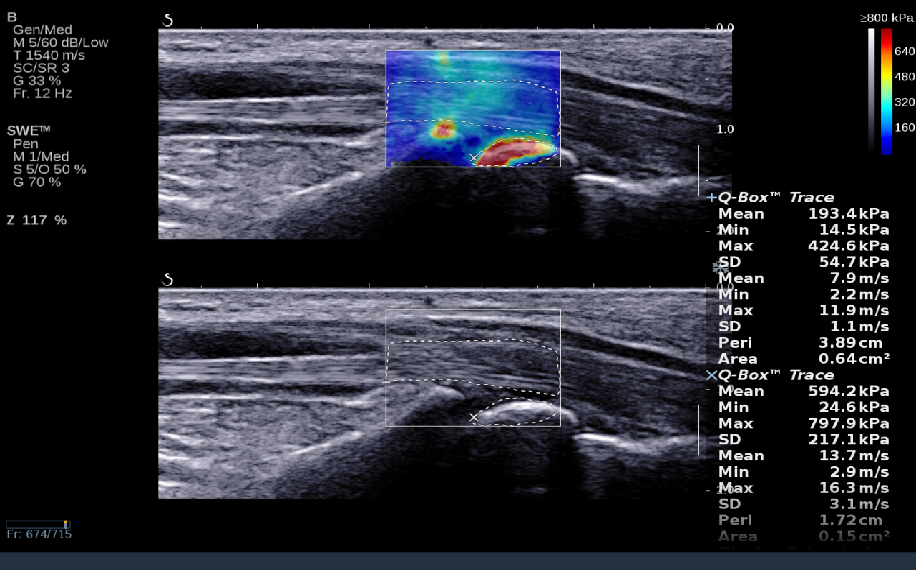

RTSWE实时剪切波弹性成像

?探头发射激励脉冲进行多点动态聚焦,利用马赫圆锥原理,形成大量的剪切波信号?颜色的变化与剪切波的速度相关,可直接体现肌肉肌腱等组织硬度值?实时、全幅、全定量

肌骨png.png

鉴别诊断、精准分级、定量评价、穿刺引导、疗效评估、随访观察